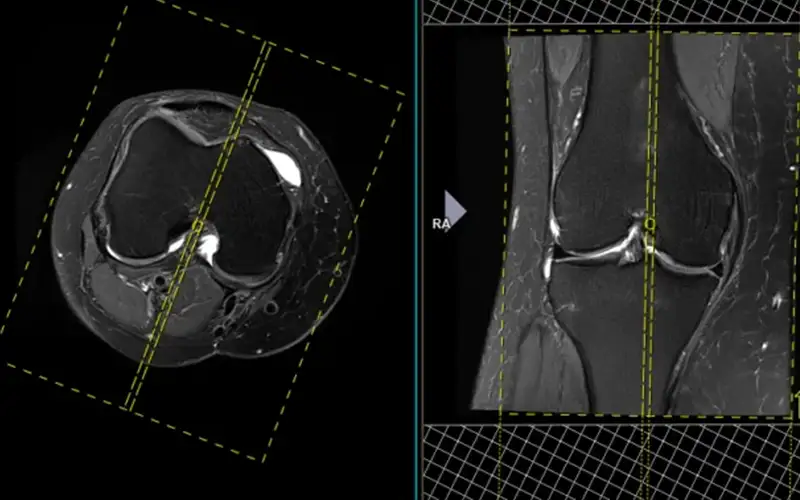

نقش MRI در تشخیص آسیبهای منیسک

امروزه MRI بهعنوان روش استاندارد و غیرتهاجمی برای تشخیص آسیبهای منیسک در نظر گرفته میشو...